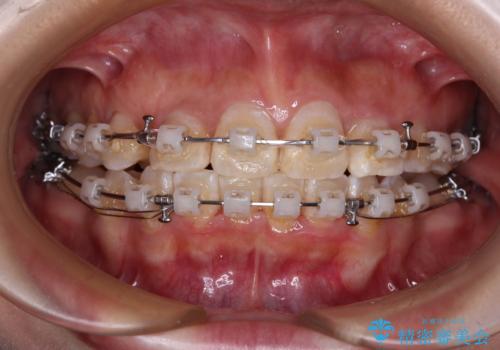

- 矯正装置

- 審美装置

下顎は第二小臼歯を抜歯したため、治療期間が長期化すると思われましたが、大臼歯が後方に傾斜していたため、容易にスペースを閉じることができ、2年強で治療を終えることができました。